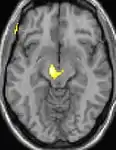

![]() | ![]() | ![]() |

| Voxel-based morphometry (VBM) shows brain area structural differences. | ||

Positron emission tomography (PET) scans indicate the brain areas which are activated during attack only, compared to pain free periods. These pictures show brain areas that are active during pain in yellow/orange color (called "pain matrix"). The area in the center (in all three views) is specifically activated during CH only. The bottom row voxel-based morphometry (VBM) shows structural brain differences between individuals with and without CH; only a portion of the hypothalamus is different.[36]